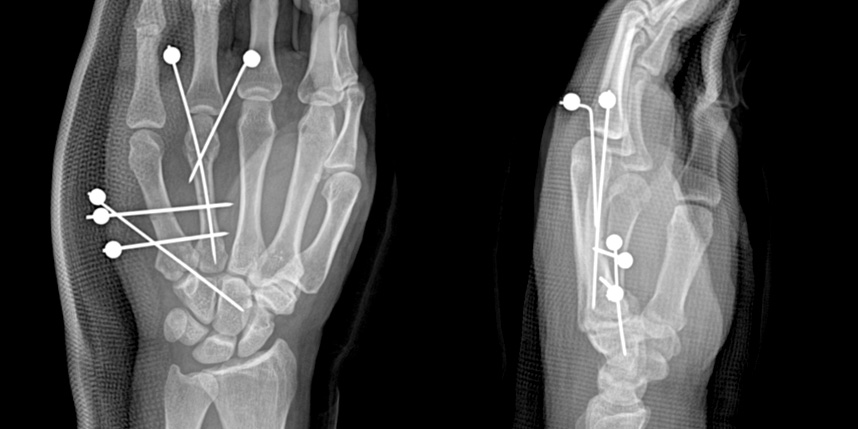

골절이 심하지 않은 경우에는 깁스로 고정해서 유합을 시킬 수 있으나, 정도가 심한 경우에는 손,발목 골절 수술을 진행할 수 있습니다.

골절은 정확하게 골절편을 잘 맞추고 고정하는 것이 중요합니다. 특히 관절면을 잘 맞추는 것이 중요합니다.

손가락 골절